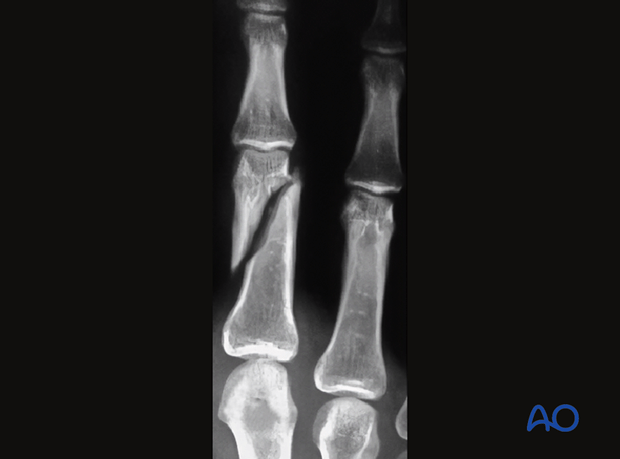

This type of fracture results in multiple bone fragments at the fracture site.

What is a comminuted fracture?